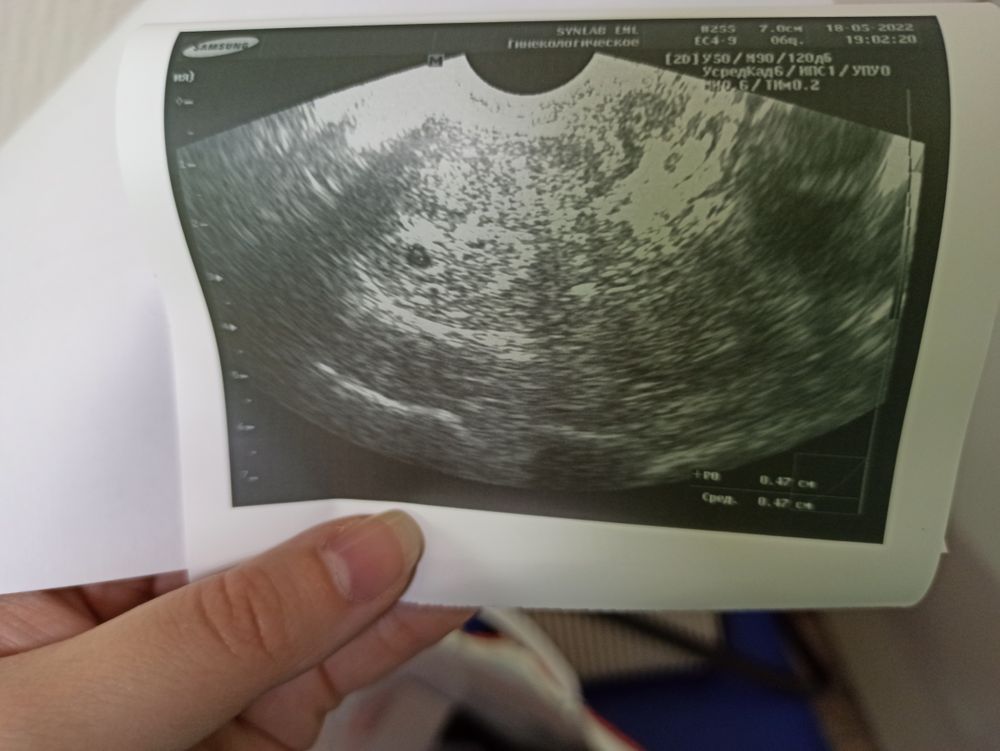

УЗИ на следующий день после ХГЧ - плодное яйцо в матке 4,7 мм, эмбрион не визуализируется, слова врача "мы не можем исключать замершую, не можем исключать внематочную" (но это ее работа и не сказать я считаю она не могла), тут я впервые в жизни узнала, что бывает и такое маточная+внематочная, причем внематочная не всегда в трубах, а может быть и в брюшной полости. После таких слов конечно начнёшь переживать, но я верила в свою точечку.

Рекомендации повторное УЗИ через 3-5 дней, посмотреть развивается ли плодное яйцо.

УЗИ через 3 дня.

Оно увеличилось, и нашелся эмбриончик, мне выдали справку, беременность 4-5 недель. Рекомендации повторить ХГЧ через неделю (шаг в два дня должен быть от предыдущего), если ХГЧ - ок, ещё через неделю на УЗИ посмотреть развитие и сердцебиение.